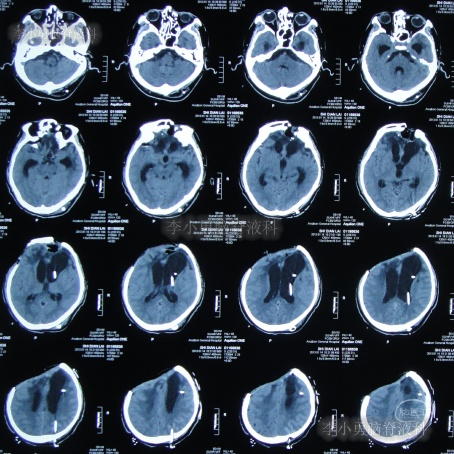

为求进一步治疗,2022年4月29日,第2次来李小勇脑脊液科治疗。入院时:意识不清,刺痛后四肢能动(图-31),查头颅CT(图-32)示脑室有扩张,有积气。

图-32:2022年4月29日头颅CT

入院后当天进行了原分流管拔除术+脑室引流术,术后当天查头颅CT示有出血(图-33)。

图-33:2022年4月29日术后头颅CT

术后5天即2022年5月3日,查头颅CT示脑室有缩小(图-35)。

图-35:2022年5月3日头颅CT

2022年5月13日(入院治疗15天),查头颅CT示脑室又有缩小(图-36)。

图-36:2022年5月13日头颅CT

2022年5月23日(入院治疗25天),查头颅CT示脑室缩小(图-37)。

图-37:2022年5月23日头颅CT

脑脊液化验变正常后于2022年9月9日(治疗133天),进行了脑室腹腔分流术(图-39)。

图-39:2022年9月9日头颅CT

2022年9月23日(李小勇脑脊液科治疗147天)出院,出院时:意识清楚,肢体活动、走路正常,住院期间脑脊液未见漏(图-40);出院前头颅CT示颅骨缺损(图-41)。

图-41:2022年9月19日出院前头颅CT